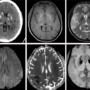

Axial NCCT image of the brain shows calcifications involving bilateral basal ganglia and thalami. Axial T1 and T2-w images show hyperintense basal ganglia and thalami, with corresponding areas showing blooming in axial SWI, consistent with calcifications (black arrows). Right parietal lobe shows a focal area of hyperintense signal involving both grey and white matter in axial T2-w image, which shows hyperintense and hypointense signals in DWI and ADC map respectively, suggestive of diffusion restriction and consistent with acute infarct (white arrows).

Final Diagnosis: FABRY’S DISEASE